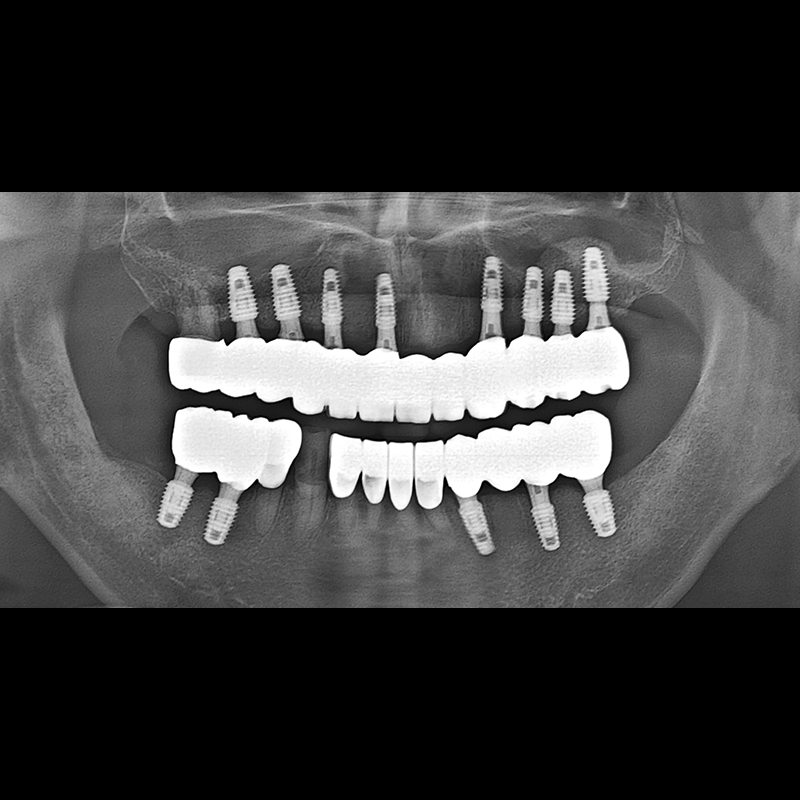

BEFORE AFTER

Implant before and after 2025.05.30

Implants were placed in the missing tooth and in the tooth position where it was difficult to save.